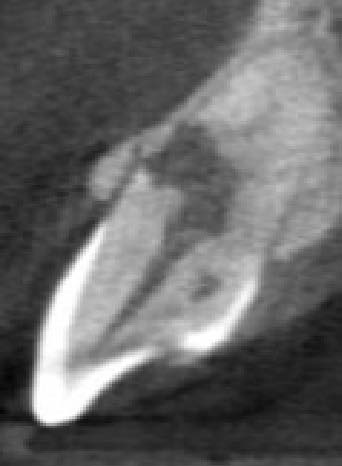

The CBCT revealed intraroot perforating resorption on the vestibular root surface. In addition, a possible cause of resorption was identified as Oehlers' Type I invagination (1957), which was based on the radiological findings. According to the classification, Type I invagination is covered with enamel and is located within the coronal part, extending no further than the enamel-dentin junction. The authors believe that the infected invagination zone with subsequent creeping infection of the root pulp brought about the resorption. The response to the cold stimulus was very insignificant, especially in comparison with tooth 12. This made it clear that an irreversible destructive process is going on in the damaged tooth. Since the patient was planning orthodontic treatment and the resorption process could grow worse, it was decided to conduct endodontic treatment.

The radiographic findings were very similar to external resorption, but some moments were not typical of it.

In favor of external resorption was the shape of the defect, with the wider defect facing the bone, the shape of the defect was not rounded, which would be characteristic of internal resorption.

Also, there were signs in favor of internal resorption. The defect was below the cervical part, which is not typical of external cervical resorption. The response to cold stimuli reduced, which is not characteristic of external resorption, as it affects the pulp only in the last stages of tooth structures decay. Furthermore, the X-ray obliteration of the root canal beyond the resorption area is not characteristic of external resorption. Visit 1: Pre-op X-ray plus anesthesia with sol. Ubisthesini 4% -1 ml, isolation with rubberdam. The access was made as close as possible to the incisal edge. When opened, at first glance the pulp chamber looked quite II.